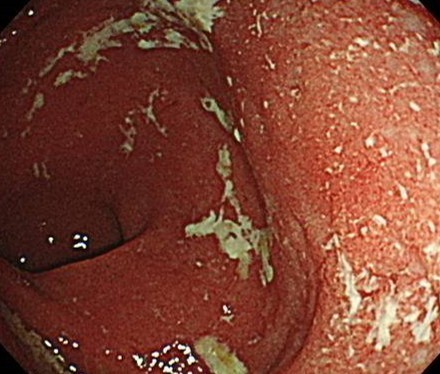

特に直腸に慢性の炎症が起こり

粘膜に潰瘍や出血をきたします

腸内の炎症の範囲や状態を直接確認し、必要に応じて粘膜の一部を採取して病理検査を行います。